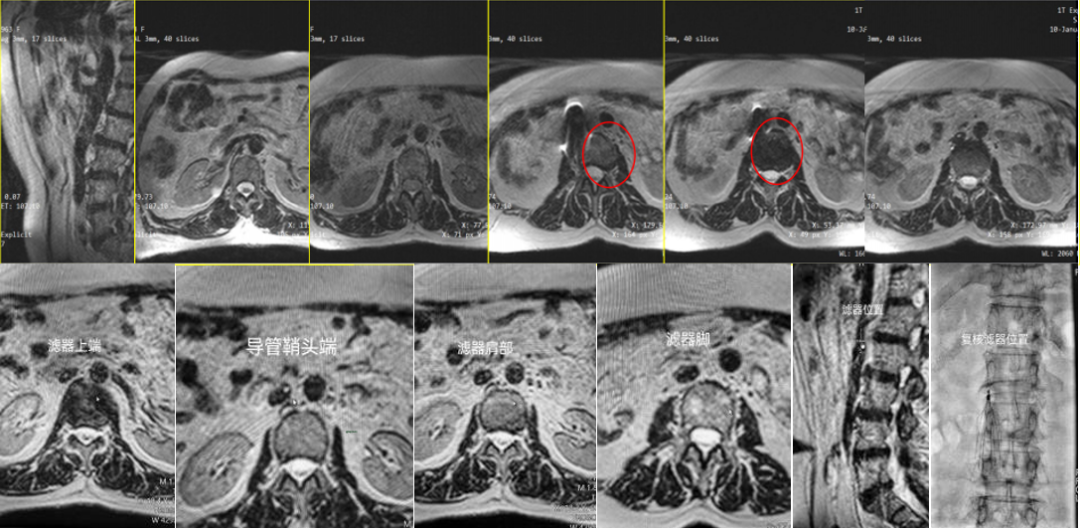

已成功应用于下腔静脉滤器植入、肝癌微波消融等手术;

DVT下腔静脉滤器植入